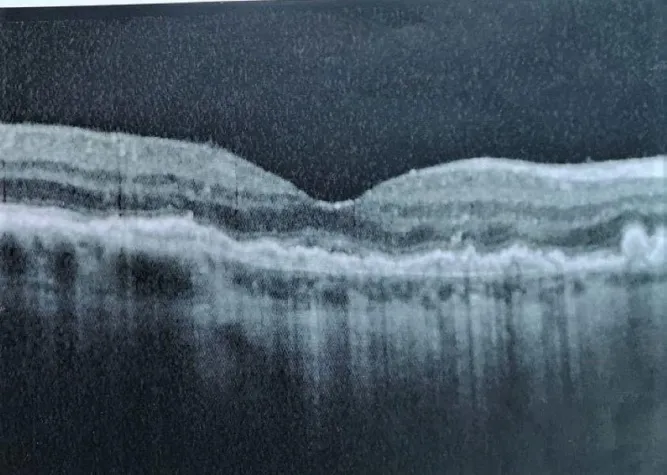

• Eine MAB-Kursteilnehmerin aus Österreich meldete ebenfalls einen au?ergewöhnlichen Erfolg bei der Heilung einer feuchten AMD: Sie behandelte ihren Mann vor zwei Jahren wonach zunächst eine Verbesserung des Krankheitsverlaufs zu verzeichnen war. Doch aufgrund von Stress und Sorgen erlitt der Patient im Juni 2019 wieder einen Rückfall. Im Zuge einer OCT-Untersuchung bei der Augenärztin wurde festgestellt, dass der Mann wieder Einblutungen in beiden Augen hatte. Nach Behandlungen mit Laserakupunktur und einer Therapie mit elektromagnetischen Feldern besuchte die Österreicherin Ende Juli 2019 einen Kursus in Augenakupunktur bei unserer Dozentin Sandra Kaim. Dort wurde der AMD-Patient zwei Tage genadelt und die darauffolgenden drei Tage wurde er von seiner Frau mit der Augenakupunktur nach Boel zuhause behandelt. Am 26. Juli hatte der Patient wieder eine Kontrolluntersuchung bei seiner Augenärztin, und diese war völlig überrascht und sprach von einem „Wunder“: Innerhalb der 5-wöchigen Behandlungszeit seit dem 19. Juni tat sich einiges - die AMD war nun völlig trocken! Die Betroffenen bezeichneten die Resultate der Augenakupunktur nach Boel als „sensationell“! (siehe Fotos mit Scan-Bildern) Die Kursteilnehmerin aus Österreich ist nach eigener Aussage „total begeistert“ von der Modernen Akupunktur nach Boel.